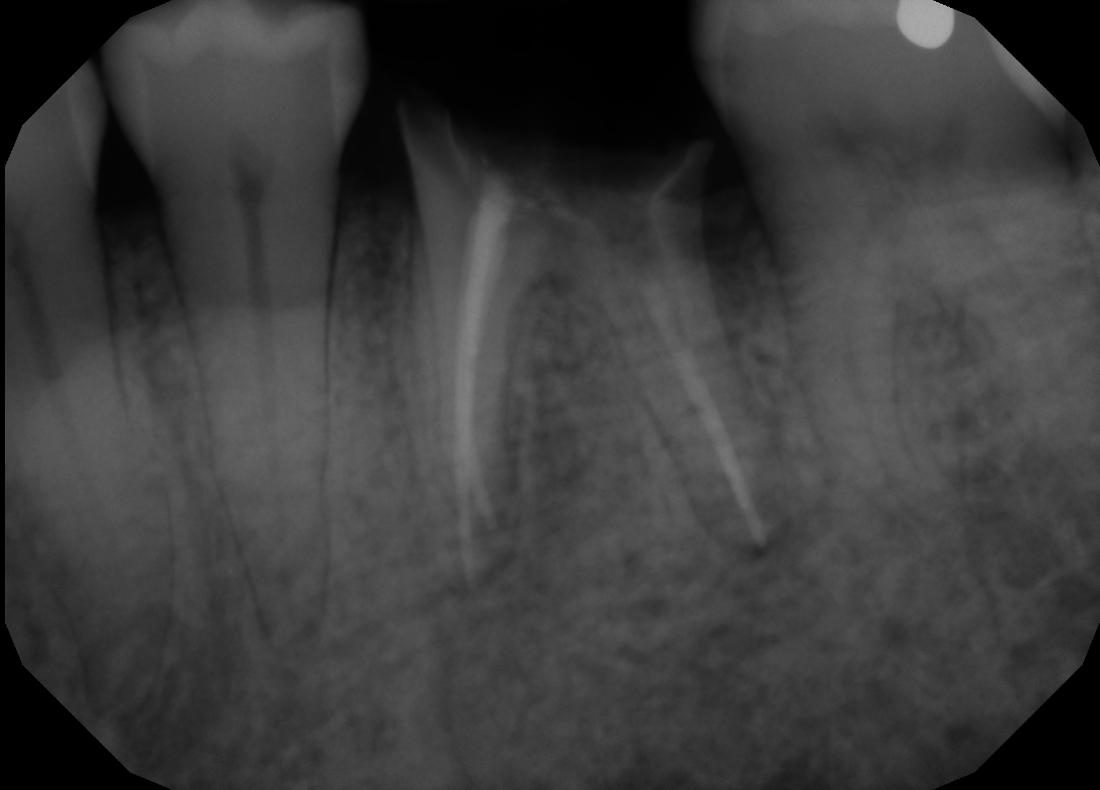

#19 Immediate Implant

Patient presents to our office with crown that has fallen out of the tooth, which was due to the lack of tooth structure to support the crown. Tooth was extracted and immediate implant was placed. With the immediate placement of implant, we were able to save patient 3 months of waiting time.